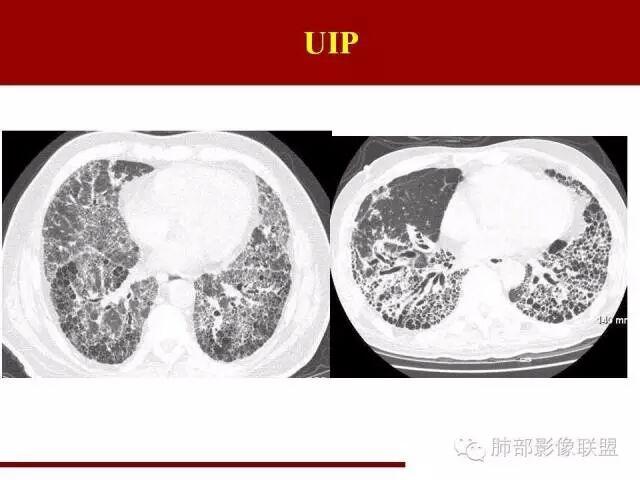

间质性肺炎影像学,间质性肺炎肺纤维化

间质性肺炎ct表现

间质性肺炎ct图片

间质性肺炎早期ct图片

间质性肺炎ct图片特点